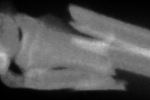

Bonifacy został naprawiony za pomocą drutu chirurgicznego. Podczas

operacji spał |